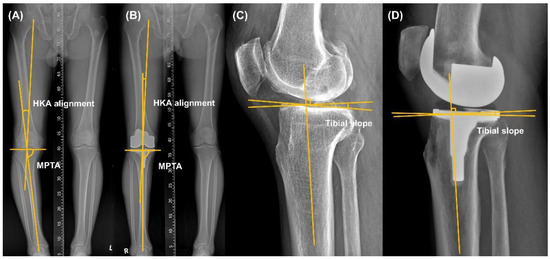

2.2. Radiographic and Clinical Assessment

2.3. Pre-Operative Planning

2.4. Intraoperative Planning